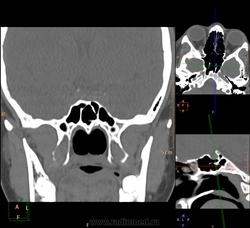

Вроде основных две, но разнообразные перегородки делят их на бОльшее количество:

Тут, например, 7 камер у одной пациентки: